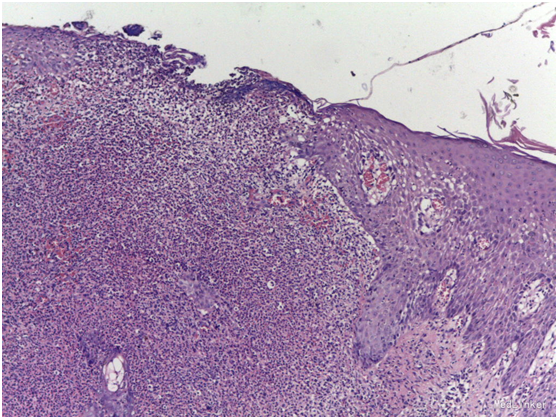

皮损:右面部可见分别4*5cm和1.5*1cm红色浸润性斑块,表面散在米粒至龙眼大小结节、脓疱。 辅助检查:初步诊断:面部皮疹性质待查:Sweet’s综合征;孢子丝菌病;淋巴瘤;其他?血常规白细胞及中性粒细胞比例升高,血沉增快;皮损分泌物镜检真菌阴性;皮肤病理:表皮局部溃破,棘细胞间海绵水肿明显,可见较多嗜中性粒细胞外渗入表皮;真皮浅层组织水肿,浅中层见大量嗜中性粒细胞浸润,其内可见破坏残留的毛囊上皮组织。符合Sweet’s综合征改变。